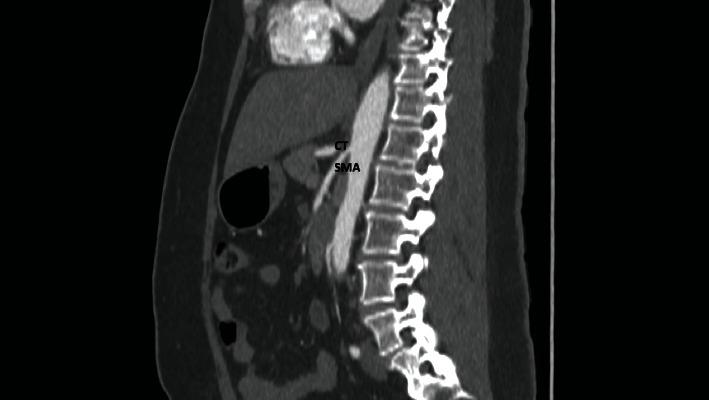

腹腔镜下松解治疗与腹腔干-肠系膜上动脉相关的正中弓状韧带压迫综合征

Laparoscopic Release for Median Arcuate Ligament Compression Syndrome Associated with a Celiac-Mesenteric Trunk.

The median arcuate ligament compression syndrome is a rare entity that occurs in 2 per 100,000 unselected individuals. We present a case where the median arcuate ligament compression syndrome was associated with an equally uncommon anatomic variation-a celiac-mesenteric trunk, which occurs in 0.42-2.7% of unselected individuals. We could find no prior report of a celiac-mesenteric trunk being associated with the median arcuate ligament compression syndrome. This report also adds to the literature to show that a laparoscopic approach to median arcuate ligament release is feasible.

正中弓状韧带压迫综合征是一种罕见疾病,在每10万名未经筛选的个体中约有2人发病。我们报告了一例正中弓状韧带压迫综合征合并同样罕见的解剖变异——腹腔干-肠系膜上动脉共干的病例,该解剖变异在未经筛选的个体中发生率为0.42%-2.7%。我们未发现此前有腹腔干-肠系膜上动脉共干与正中弓状韧带压迫综合征相关的报道。本报告还补充了文献资料,表明腹腔镜下正中弓状韧带松解术是可行的。